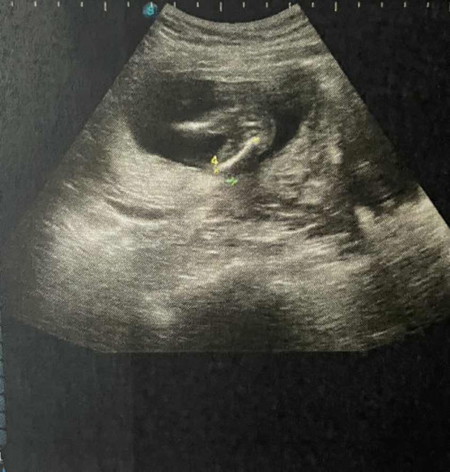

น้องเป็นผู้หญิง หรือ ผู้ชายค่ะ

น้องน่าจะนอนหันตูดใส่เลยดูไม่รู้เลยค่ะ แม่ๆว่าน้องเป็นเพศไหนคะ 😊😊

รอดูรอบหน้านะแม่ 🤣